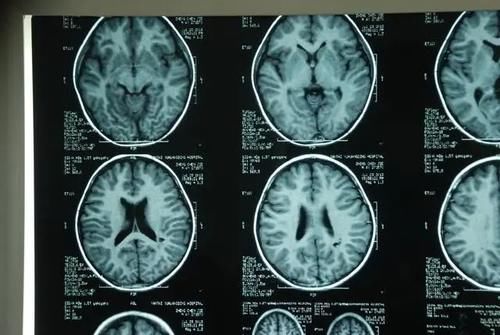

常见的检查方法除了临床试验B超、CT检查之外,还有核磁共振等等,这些检查可以从不同角度最大程度地了解患者身体情况。

检查报告出来后,一般会成为医生研究病情、对症下药的最有力的参考。但是很多人应该都听说过,体检中医生一般建议患者尽量不要做核磁共振。

众所周知,治病 讲究的就是对症下药。不同疾病不仅采取的治疗方式不同,其检查方式也不尽相同。核磁共振适用检查的病情有心血管疾病,神经系统疾病等等。